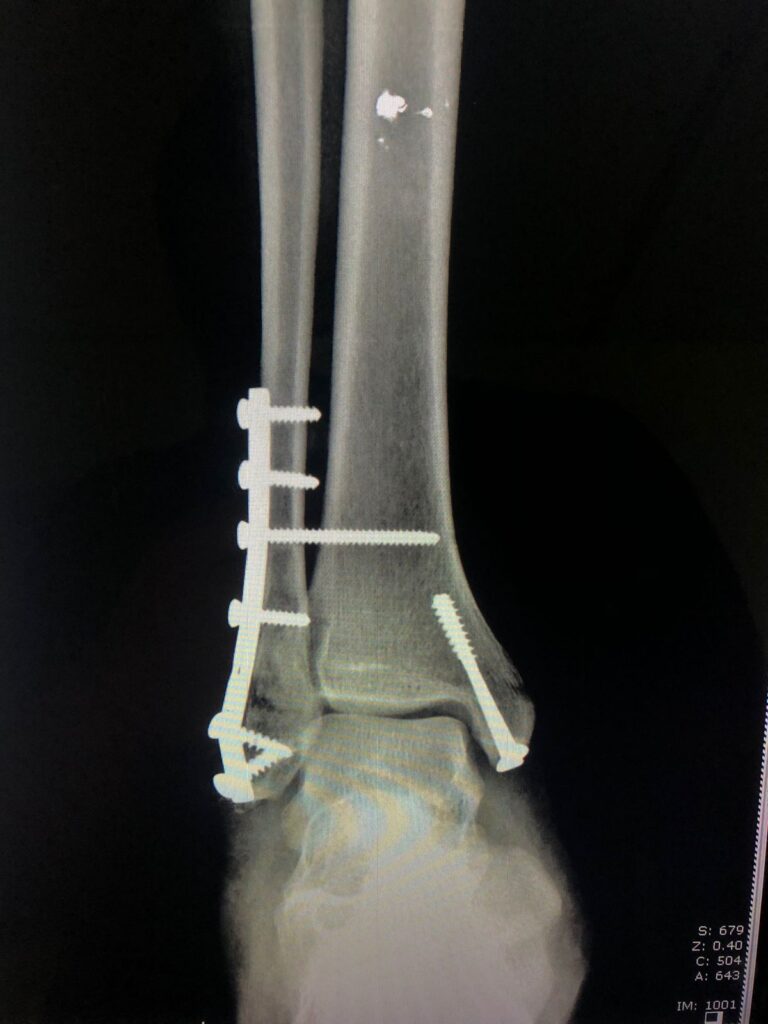

Fracturas de pie y tobillo.